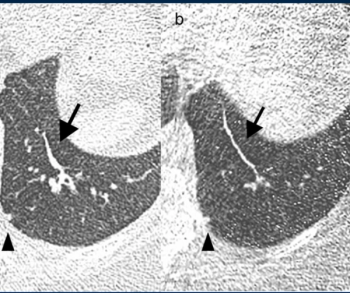

People who smoke marijuana and cigarettes have 12 times the risk for centrilobular emphysema than non-smokers, according to new computed tomography (CT) research presented at the annual Radiological Society of North America (RSNA) conference.

Ultra-low-dose computed tomography (ULDCT) may have similar efficacy as low-dose CT (LDCT) for detecting a variety of pulmonary conditions in people with current or past smoking histories, but had poor detection of ground glass opacification lesions, according to a recent prospective study presented at the Radiological Society of North America (RSNA) conference.